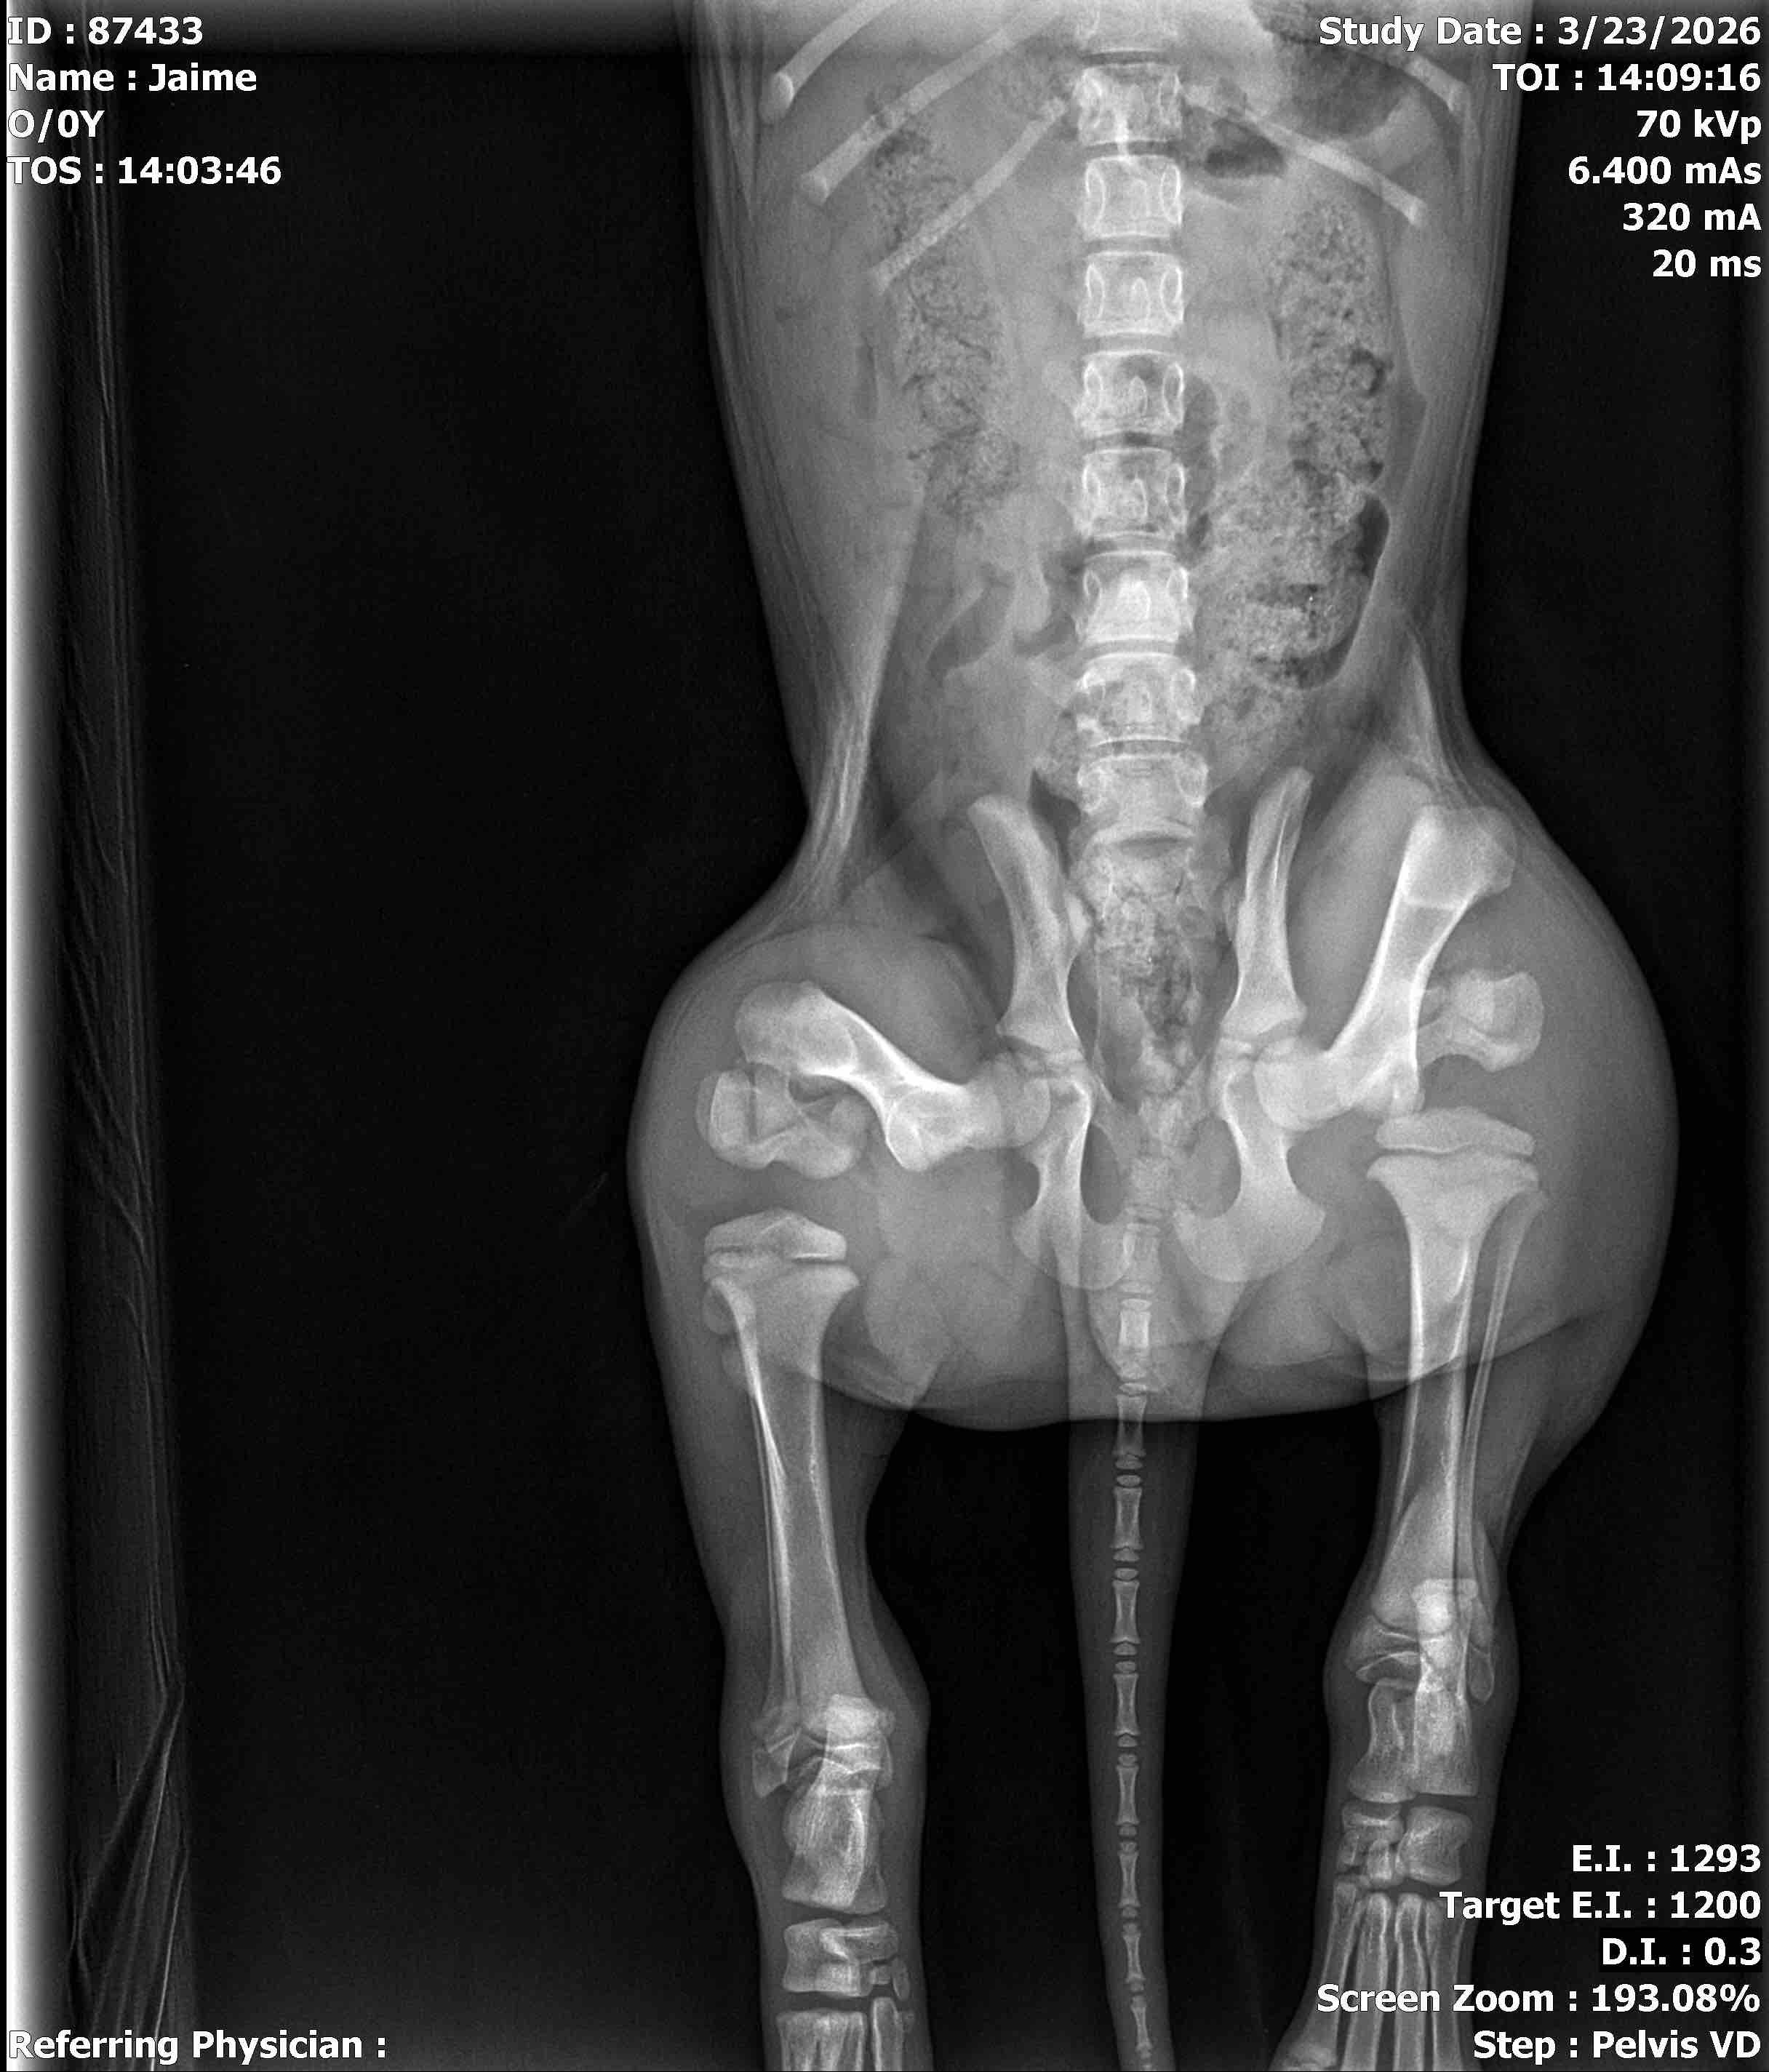

Hi, my name is Adrian, and I am raising funds to help my dog Toby get the surgery he urgently needs. Toby was recently hit by a car and suffered two broken femurs. He is in a lot of pain and currently cannot walk on his own.

Toby is a loving and happy dog who means everything to me. Seeing him hurt like this has been heartbreaking. The surgery he needs to repair his legs costs about $7,000, which is more than I can afford right now, especially at 17 years old. I am doing everything I can to try to save him and give him the chance to walk and live a normal, happy life again.

The funds raised will go directly toward Toby’s surgery, medical care, medications, and recovery. This surgery will help stabilize his legs so his bones can heal properly and relieve the pain he is experiencing.